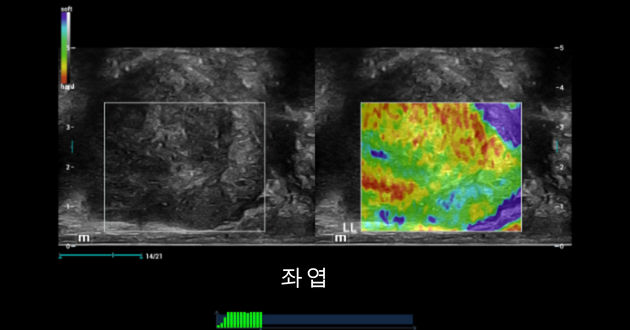

??? ??? ????? ?? ?? ??-?? ??? ???? ???? ???????. ????? ?? ??? ?? ?? 2?? ??? ???? ???, ???? ???? ?????, ???? ????? ????? ??? ?? ? ?????. ???? ???????(NTE: Natural Touch Elastography)? 2D ?? ?? ???(STE: Sound Touch Elastography)? ??? ??????? ??? ?? ??? ????? ?? ???????.

STESWE ŌĆō ??? ?? ???:

??? ?? ???(SWE)? ??? 34kPa, ??? 115kPa? ?? ??(??6). ?? ??? SWE? ???? ? ???? ? ??.(?? = 19 kPa, ?? = 36 kPa). (??7) ????? ??? ????(PZ)?? ???? ?? ???? ???. ????(TZ)? ??? ???? ?? ????(PZ)?? ? ???. ????(TZ)? ????(PZ)? ??? ???.

- STE? ??? ???? ???? ??????, ?? ???? 34kPa, ??????? 115kPa????.

- ?? STE? ??? ?? ?? ???? ??????, ?? ???? 19kPa, ?? 36kPa????.